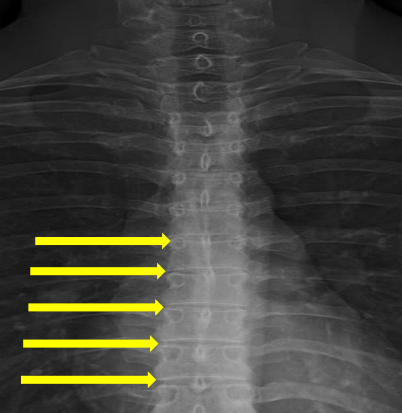

Pedicle shadows

Vertebral waist

Inferior endplate tips

Superior endplate tips

Disc spaces

End plate tips